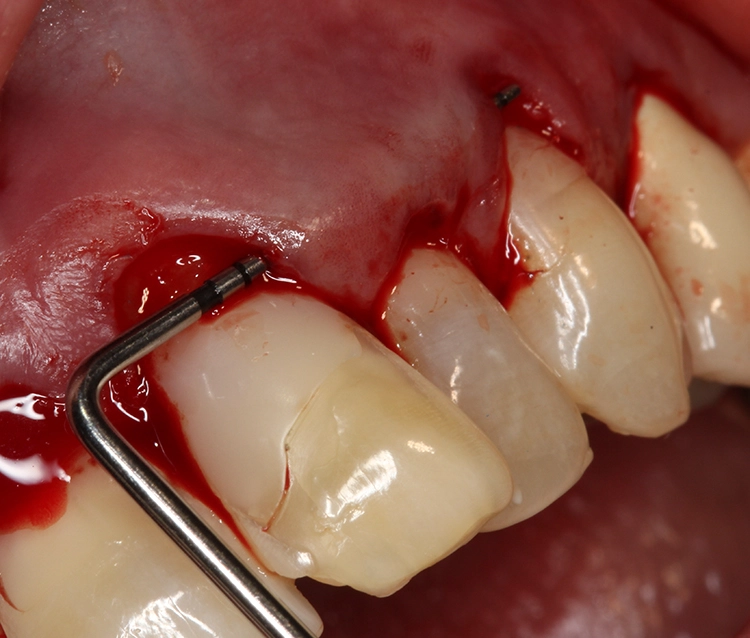

So sollte an den Zähnen 21 und 23 eine Rezessionsdeckung mit Verdickung des Gewebes und an Zahn 22 eine chirurgische Kronenverlängerung durch Exzision der Gingiva ohne Osteotomie erfolgen (Low-Crest-Typ). Der Verlauf der Schneidekantenlängen und die Zahnstellung sollten in einem 2. Schritt durch Vollkeramikteilkronen bzw. Veneers mit Inzisalfassung harmonisiert werden. In der Behandlungsplanung dieses Falles kam erschwerend hinzu, dass 3 verschiedene parodontalchirurgische Behandlungsindikationen zusammenkamen:

Bei Patienten vom Low-Crest-Typ beträgt der Abstand zwischen Gingivarand und Knochen vestibulär mindestens 3 mm, interproximal mindestens 5. Daher führt bei diesen Patienten unter Umständen eine einfache Exzision von Gingiva ohne Knochenchirurgie bereits zu einem zufriedenstellenden Ergebnis.

Je nach Breite der keratinisierten Gingiva wird dann über die Operationstechnik entschieden. Ein apikal verschobener Mukosalappen findet bei einer Breite von weniger als 2 mm Einsatz, während bei einer Breite von mehr als 3 mm ein voller Mukoperiostlappen präpariert wird.